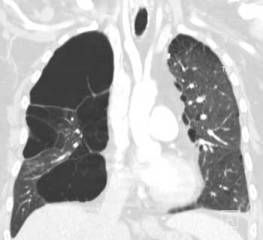

A CT scan of the thorax was ordered to help determine whether a recurrent pulmonary embolism may have contributed to the arrhythmia (Figures).

The patient also had a more than 20-year history of giant bullous emphysema (GBE). He had undergone a left-sided bullectomy in his 40s to help alleviate symptoms. He has continued to smoke and the disease has progressed.

GBE, or “vanishing lung syndrome,” is a rare condition typically found in young men who smoke. It is caused by paraseptal emphysematous bullae that coalesce and eventually compress the lung parenchyma.1 By definition, the bullae must occupy at least one-third of the hemithorax and thus can be mistaken for a pneumothorax on a standard chest film.2